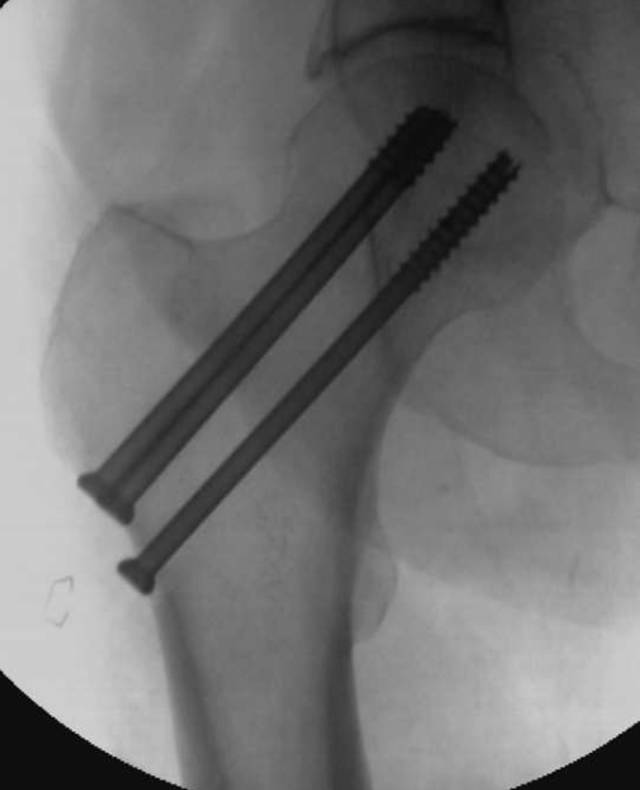

图3C-65岁的男子在地面摔倒后,在射线照片上没有看到移位性骨折。用三个压紧螺钉将骨折内部固定。

陷阱9:硬件放置后的骨折

骨折评估在硬件放置后的患者中是具有挑战性的,例如由于各种原因的骨折固定或关节置换所见[45,46]。密集重叠的金属密度可以限制硬件骨折或假体周围骨折的可视性。倾斜视图通常是有帮助的。诸如CT或MRI的横截面成像可以受到金属伪影的限制,并且应当在可用时使用修改的金属伪影减少协议来执行。硬件植入物改变宿主骨上的应力,导致应力屏蔽发生时的慢性骨丢失和应力集中的骨肥大。当经受创伤时,力倾向于集中在植入物和骨之间界面的位置。断裂通常在那些界面处开始,然后远离集中点传播。例如,髋关节植入物患者中的股骨骨折通常穿过股骨柄的尖端(图11)。通过具有内固定的骨的骨折通常穿过板的末端处的皮质。

图11A、B -54岁左侧全髋关节置换术的男性。A,骨盆正位片(A)和左侧髋部青蛙侧视图(B)显示股骨中轴延伸到股骨柄尖水平的倾斜骨折(箭头B)。